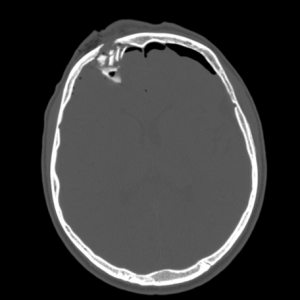

ПЕРЕЛОМЫ ЧЕРЕПА НА КТ

Изменения костей черепа травматического характера четко и достоверно выявляются при компьютерной томографии головы: можно оценить характер перелома, направление линий перелома, глубину импрессии (вдавления костных отломков), количество костных отломков, их размеры, форму, положение.

Перелом правой лобной кости на КТ. Виден вдавленный перелом свода черепа, воздух в эпидуральном пространстве.

Трехмерная реконструкция черепа при КТ визуализирует сложный перелом правой височно-теменной области.